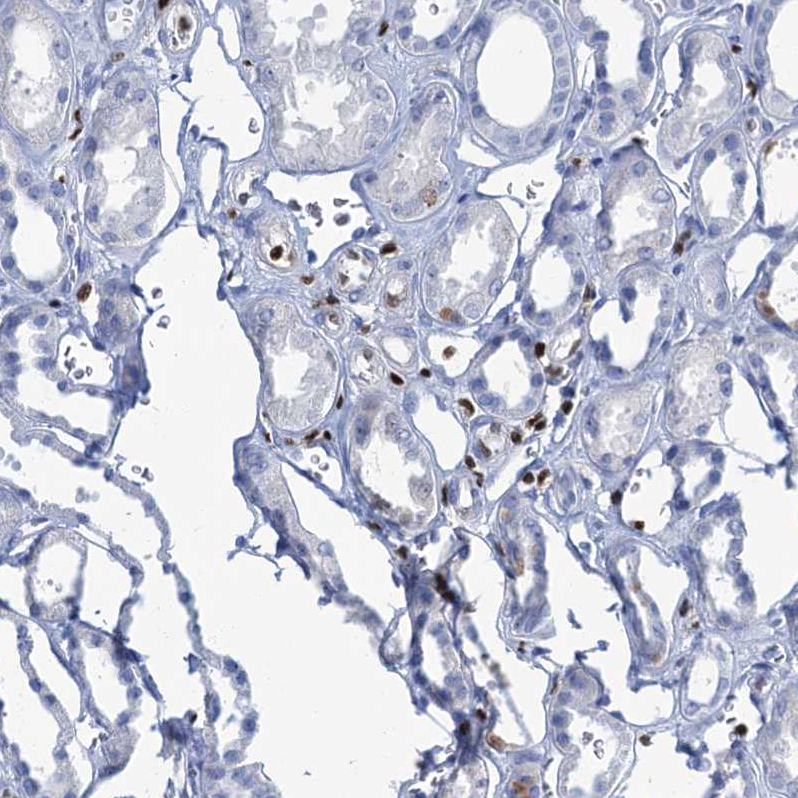

Immunohistochemistry analysis in human cerebral cortex and kidney tissues using HPA035813 antibody. Corresponding CELF2 RNA-seq data are presented for the same tissues.